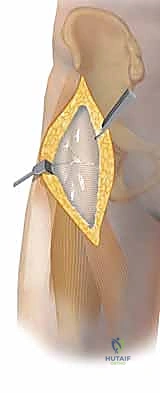

- النهج الأمامي (سميث بيترسون - Smith-Petersen Approach): يتم العمل في المسافة الفاصلة بين العضلة الموترة للفافة العريضة (Tensor Fasciae Latae) جانبياً والعضلة الخياطية (Sartorius) إنسياً. في العمق، يتم سحب العضلة المستقيمة الفخذية إنسياً. تقع العضلة الحرقفية المحفظية عميقاً ويجب إزاحتها لكشف محفظة المفصل. تعبر الأوعية الفخذية المنعطفة الوحشية الجزء البعيد من الجرح وتكون بمثابة علامة تشريحية. يقع العصب الفخذي إنسياً، وغالباً ما يُصادف العصب الجلدي الفخذي الوحشي سطحياً؛ ويجب حماية كلاهما بصرامة.

بناءً على الأشعة المقطعية ثلاثية الأبعاد، يحدد الدكتور هطيف مسار الدخول:

* إذا كان الكسر في الجزء الأمامي من رأس الفخذ، يستخدم النهج الأمامي (Smith-Petersen) لأنه يوفر رؤية ممتازة دون الإضرار بالإمداد الدموي الخلفي الحيوي.